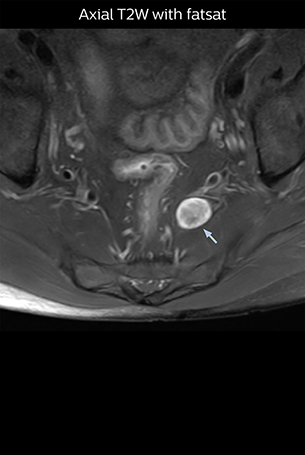

At Northern Fukushima Medical Center in Japan, excellent MRI visualization of nerves helps support confident diagnoses and informs surgical treatment decisions for patients with lower limb symptoms. MRI technologist Tanji and orthopedic surgeon Dr. Yabuki share how direct nerve visualization with the 3D NerveVIEW method adds information when diagnosing atypical herniations. The additional insights changed their way of working and benefit their patient care, as illustrated by some clinical examples.

“In patients with lower extremity neurological symptoms, NerveVIEW helps us to determine the disease matching the patient’s symptoms by directly visualizing the nerves. We use the sequence mainly, when there is suspicion of intraforaminal stenosis, extraforaminal stenosis or lateral disc herniation, which is often based on routine T2- and T1-weighted images. Additionally, the excellent depiction of the course of nerves makes NerveVIEW a good navigator when applying treatment such as block therapy or surgery.”

“Although symptoms of typical disc herniation and atypical hernia are very similar, the actual site of herniation is different. It is therefore important to characterize the nerve’s condition both inside and outside of the intervertebral foramina. “Conversely, if we see no abnormality in NerveVIEW, we can assume at least that there is no severe condition that requires surgery. Like this, it can help us avoid unnecessary surgery. NerveVIEW can have a tremendous impact in this way.”

“NerveVIEW is really useful for those cases where a nerve disorder is strongly suspected based on the clinical examination but our regular MRI images do not show any findings. These atypical herniations and spinal canal stenosis, occurring in 5% to 15% of the total lumbar herniation/stenosis cases are our main target when using NerveVIEW,” says Dr. Yabuki.

“The intra-luminal signal of veins, especially around the intervertebral space, can be suppressed well with NerveVIEW. As a result, we can easily observe the detailed nerve structure around the posterior ganglion,” he says. “This is why we use 3D NerveVIEW for intraforaminal stenosis and extraforaminal stenosis/herniation (lateral disc herniation). On the other hand, if herniation is suspected to exist inside the dorsal root ganglion (DRG), balanced TFE or ProSet-FFE is applied. NerveVIEW is not suitable for evaluating the median type of herniation.” The SE-EPI DWI-based method for MR neurography works well for large FOV exams like whole-body MRI, but focal examination of nerves is often limited by the attainable spatial resolution (both inplane and slice direction) and geometric distortion. “3D NerveVIEW achieves higher in-plane resolution – close to our other routine spine sequences – and the source images can be used instead of adding a fat-suppressed T2-weighted sequence,” Tanji says.